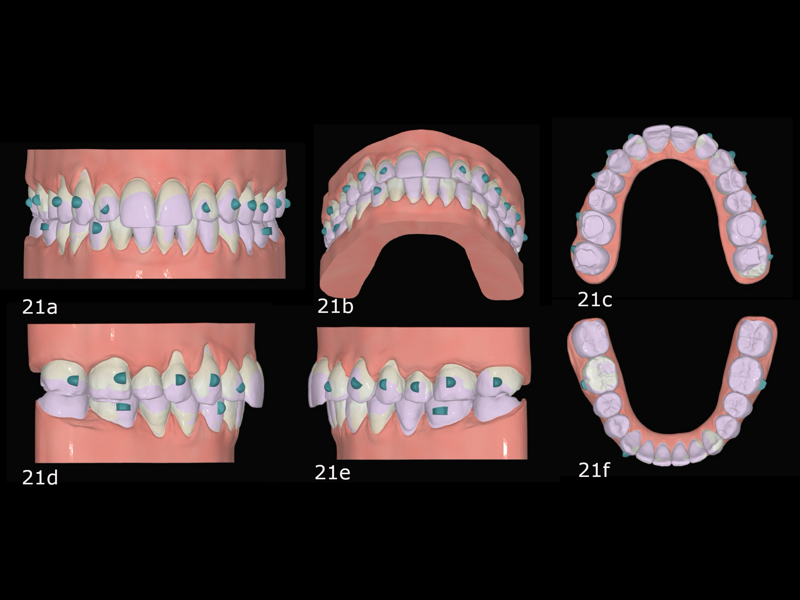

Figs. 45a–d: Pretreatment situation (purple) and expected post-treatment situation (white) in FAS OcclusalDesign.

The treatment plan with FAS consisted of aligning and levelling both arches, recovering arch forms and introducing positive torque to the entire maxillary arch, intruding the maxillary posterior teeth with the help of skeletal anchorage (vertical control) to correct the Class II malocclusion and opening space for the lateral incisors for their restoration (Figs. 45 & 46).

Because the treatment had distributed the spaces between the maxillary incisors, it was decided to provisionally restore the lateral incisors (Fig. 48). After the incisors had been restored with provisional composite, we scanned the patient for new aligners to initiate the second phase. In this phase, we expanded the maxillary and mandibular arches, continued the postero-superior intrusion to close the open bite by mandibular auto-rotation and finalised the alignment (Fig. 49). This stage consisted of 20 pairs of aligners (Fig. 50). We finished the case with a third phase of ten pairs of aligners and incorporated inter-maxillary elastics (Fig. 51).